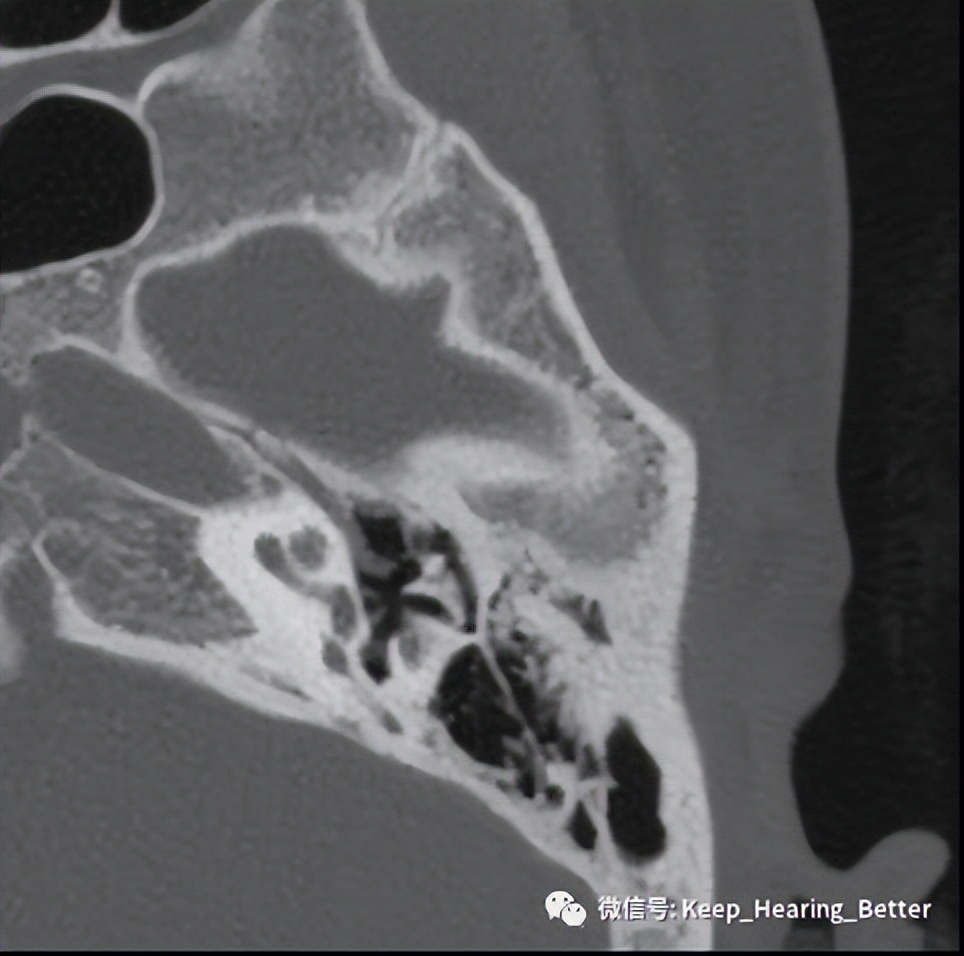

影像学检查一般选择颞骨薄层CT扫描,早期可无明显影像学阳性表现,如上图所示为此案例左耳CT影像表现。